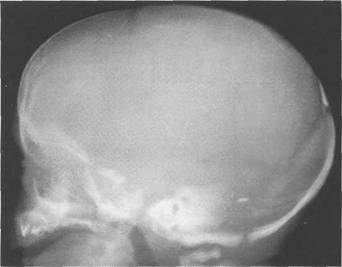

стояния теменных костей по сравнению с чешуей лобной и затылочной костей, а также на-ползания теменных костей на лобную и затылочную. Это отчетлив 121h711b о видно на боковой кра- на одном уровне. У здорового ребенка не должно быть ни их разновысокого стояния, ни,

взаимного захождения костей.